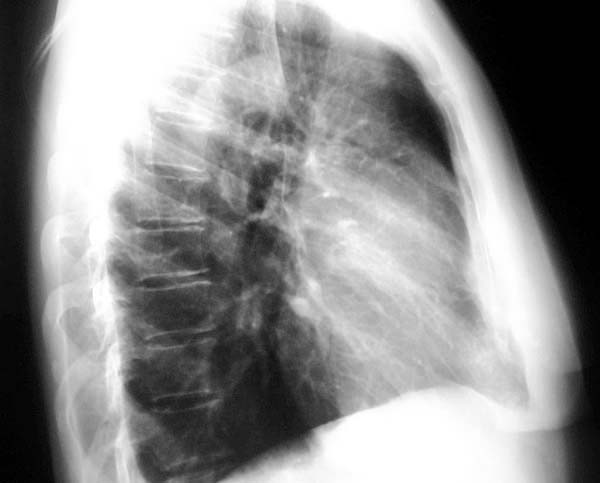

Placa 29

Comentario: se ve claramente la gran masa en el mediastino anterior en contacto con el corazón. En este caso se trata de un timoma.

Pase a al placa 30 y describa las características más llamativas de la masa.